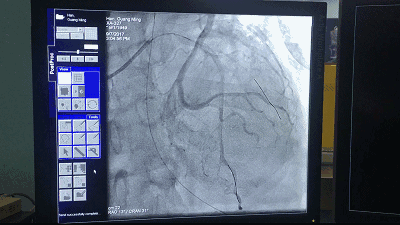

介入手术影像,网络图片 方主任又提到了先前的一个心肌梗死病例,患者